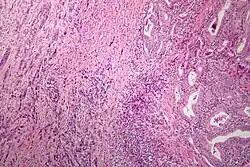

| Microscopic image of anaplastic thyroid carcinoma. H&E stain. | |

Anaplastic tumors have a high mitotic rate and frequently invades the local blood and lymphatic vessels.[5] Cellular death is frequently visualized on microscopic images.[2] The presence of regionally swollen lymph nodes in older patients in whom needle aspiration biopsy reveals characteristic vesicular appearance of the nuclei supports a diagnosis of anaplastic carcinoma. Microscopic images of ATC usually show inflammatory cells from the immune system such as T cells and macrophages.[2]

On immunohistochemistry testing, ATC is usually positive for the keratin, p53, and PAX8 proteins and is negative for thyroid transcription factor-1, thyroglobulin, and calcitonin.[2] ATC cells demonstrate high levels of PD-L1 expression.[2] BRAF and TERT mutations are seen more commonly in ATC than in differentiated thyroid cancer.[2]

ATC is divided into several different subclasses based on its microscopic characteristics. These include sarcomatoid, squamoid, osteoclastic, paucicellular, rhabdoid, and carcinomasarcoid variants.[2] As of 2019, despite the fact that these ATC subtypes are recognized, this classification has not led to differences in management.[2] ATC is always considered to be stage IV when it is diagnosed.[6]